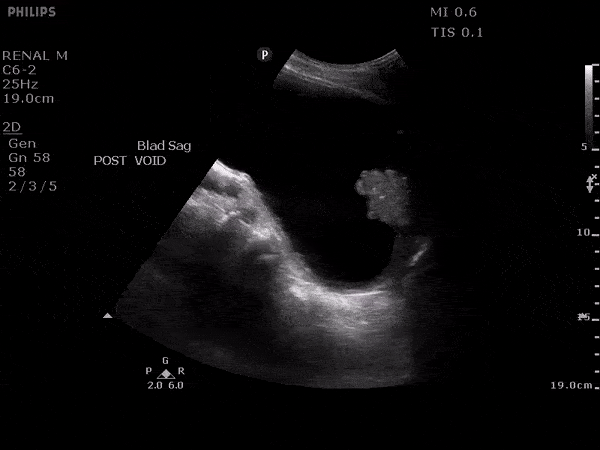

Renal/GU - Bladder cancer

Older male presented with right flank pain and hematuria. Bladder ultrasound revealed mass in bladder with internal color flow. Subsequent CT imaging performed and patient eventually diagnosed with bladder cancer. Image courtesy of Robert Jones DO, FACEP @RJonesSonoEM Director, Emergency Ultrasound; MetroHealth Medical Center; Professor, Case Western Reserve Medical School, Cleveland, OH View his original post here